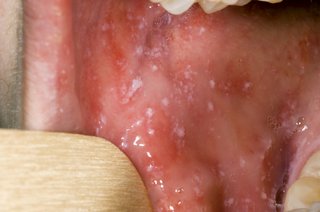

Small grey-white spots in your mouth

Not everyone with measles has these spots. The spots usually appear before the measles rash. If you have these spots and other symptoms or a rash, it's very likely you have measles.

The spots usually last for a few days.

An open mouth with small greyish-white spots on the inside of the cheek

Spots in mouth